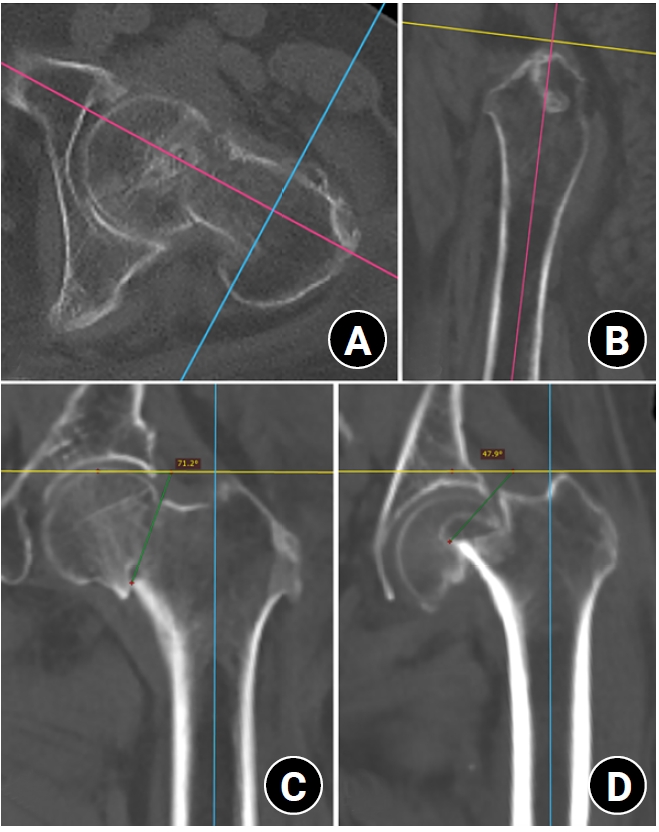

Computed tomography plane reformatting to reduce projection error in measuring Pauwels angle of femoral neck fractures: a cross-sectional study

Gyu Min Kong, Jae-Young Lim, Se-Lin Jeong, Gu-Hee Jung

J Musculoskelet Trauma 2026;39(1):38-47.

Gyu Min Kong, Jae-Young Lim, Se-Lin Jeong, et al.